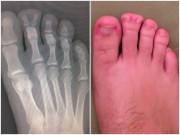

Hình ảnh minh họa về biểu hiện chấn thương dương vật.

Các biểu hiện tổn thương dương vật thường người bệnh có thể tự cảm nhận, phát hiện được như nghe tiếng kêu “rắc”, “khục” khi quan hệ, rất đau, dương vật xìu xuống, sưng nề tím toàn bộ dương vật, có thể lan xuống bìu, dương vật cong lệch sang 1 bên, chảy máu đỏ tươi qua lỗ tiểu, đái khó hay bí đái…